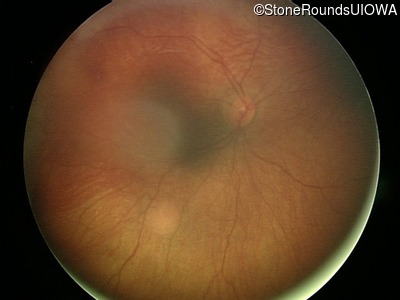

Fundus Photography - Left - UCSUM

Exemplar